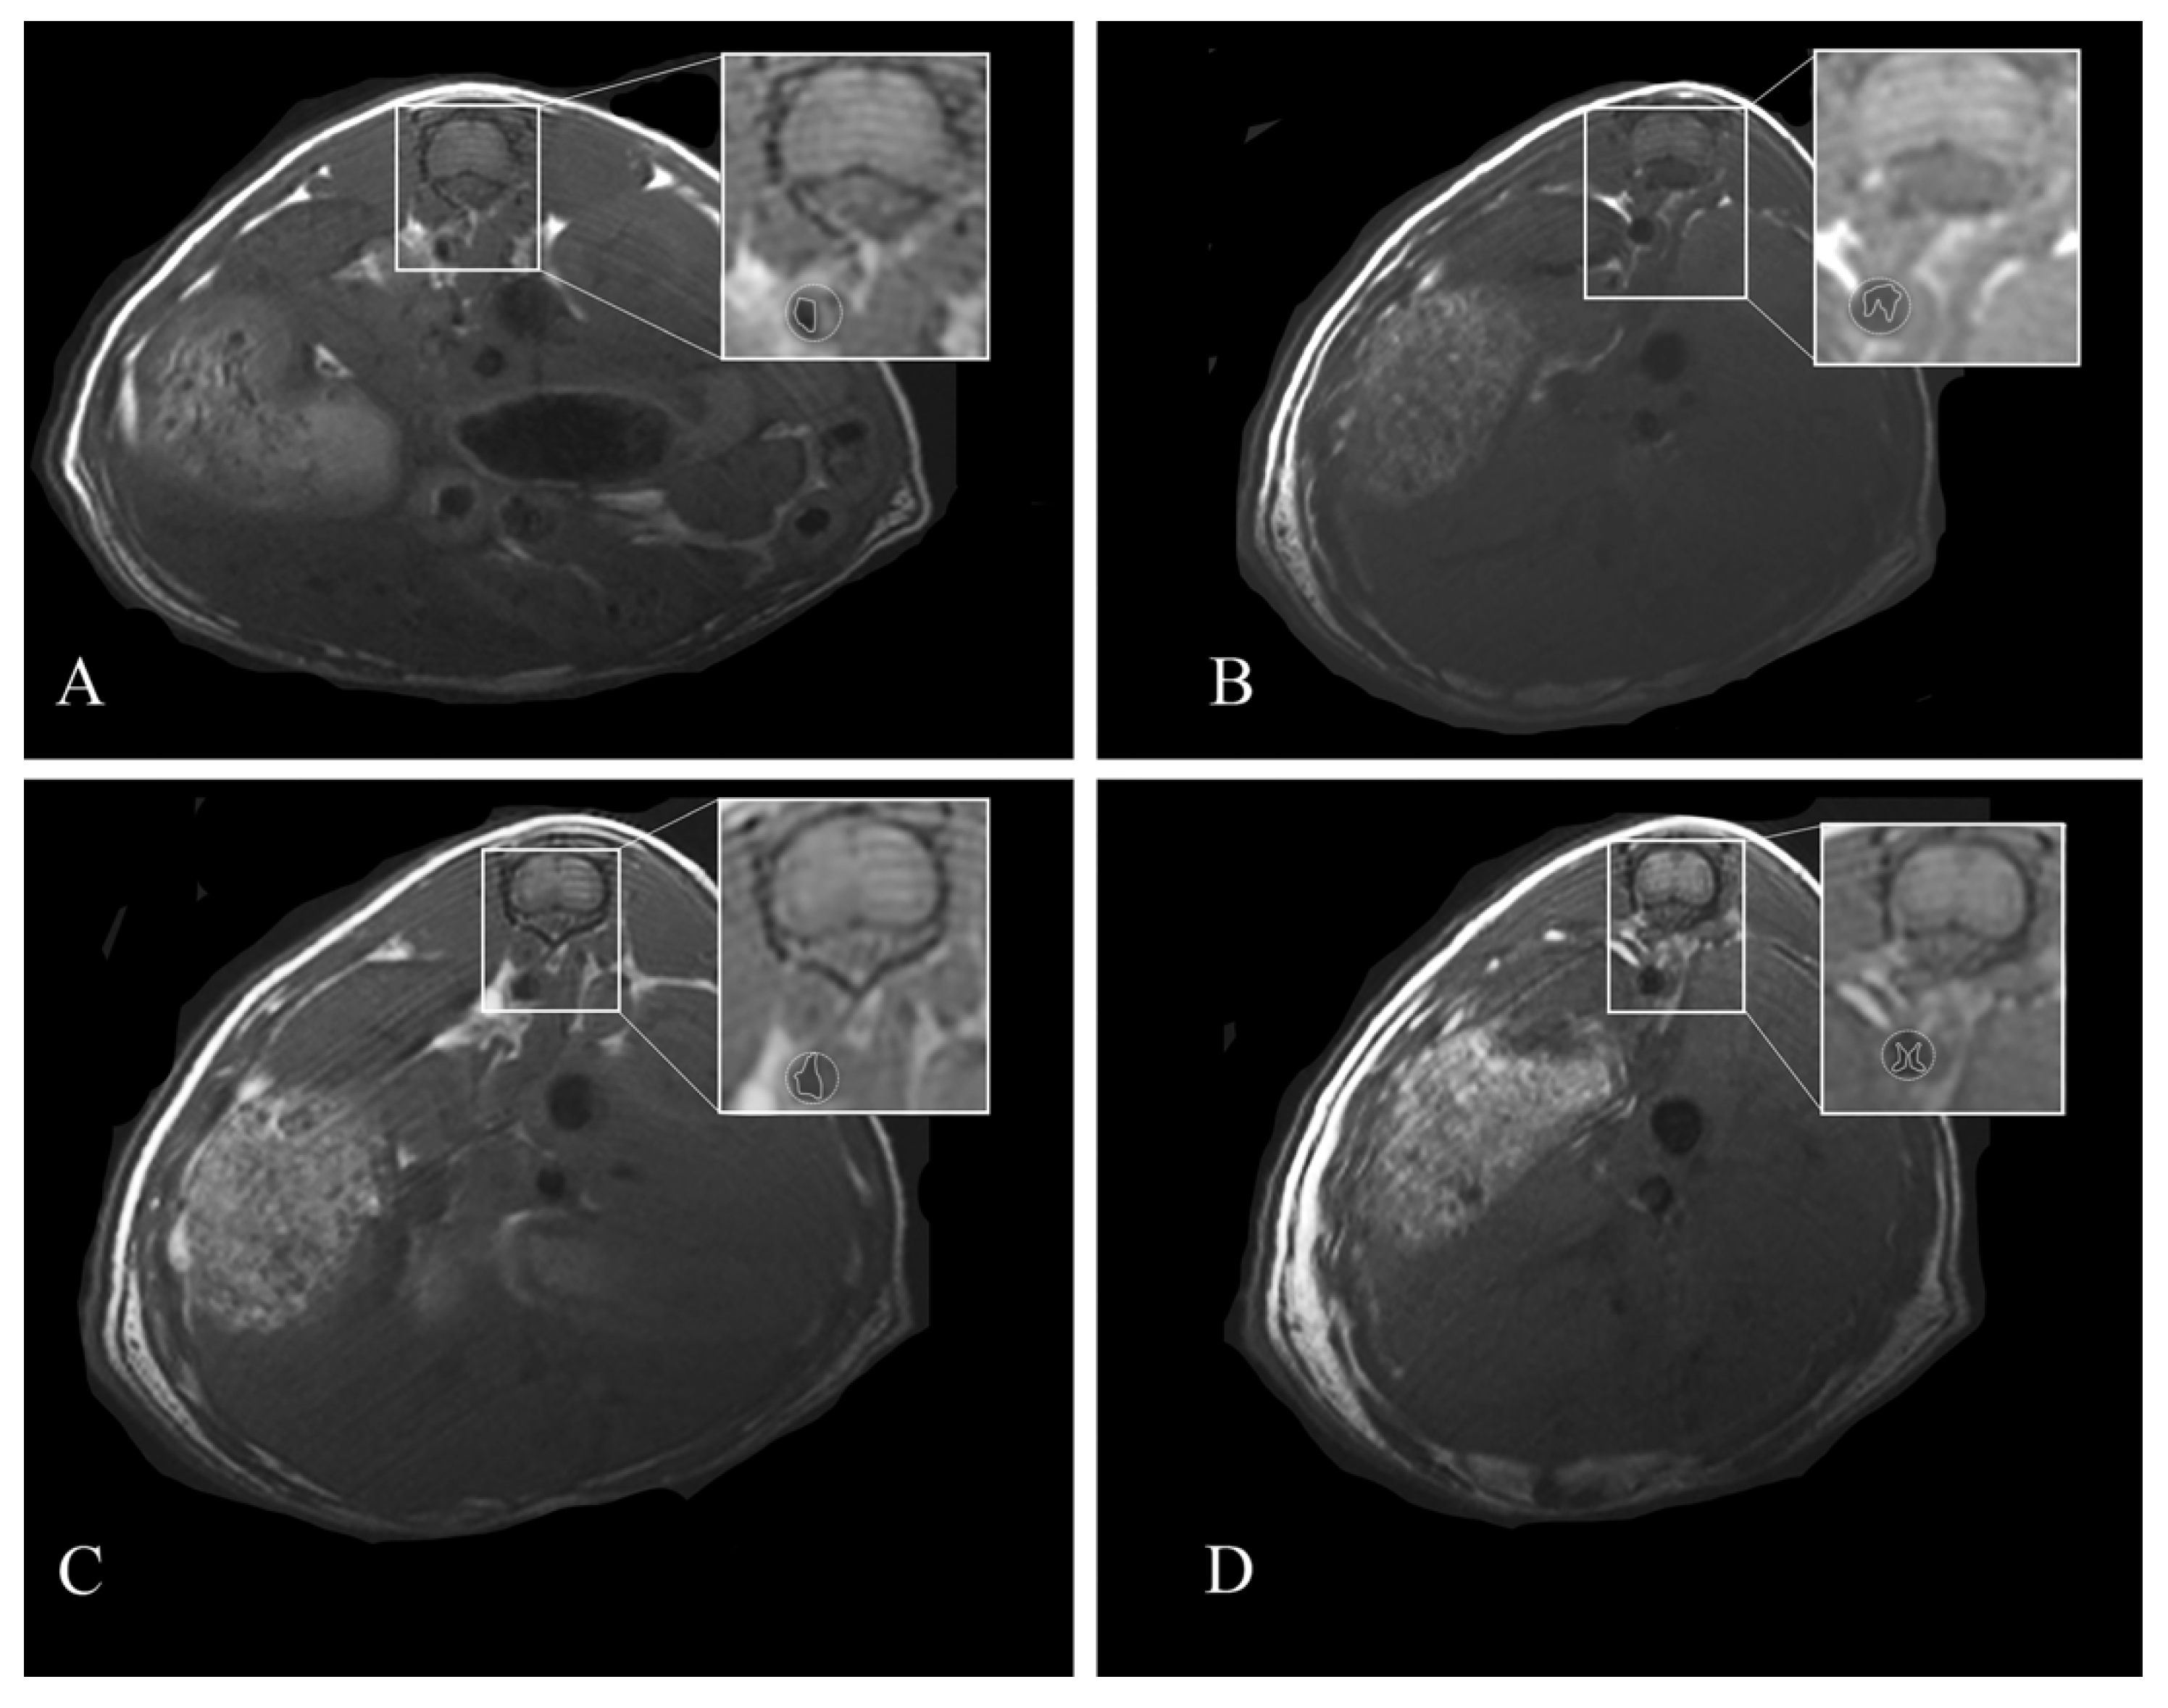

2.4. Magnetic Resonance Imaging

3.2. HFUS and MRI Monitoring